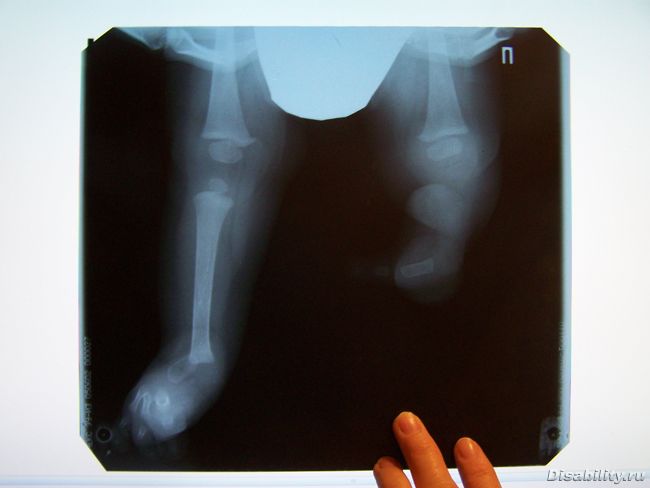

Сегодня отвез флэшку с фото рентгена в ИМР, но ничего определенного мне не сказали. Подтвердили очевидное - нет малоберцовой косточки на длинной ножке, на укороченной - нет ни больше ни малоберцовых косточек. Т.к. рентген сделан несколько не по правилам, что-либо увидеть на укороченной ножке в районе стопы не получилось. Единсвтенное, когда приедете, тогда поедем в ИМР и сделаем нормальные фотки и тогда и скажем и поймем, что делать и как.